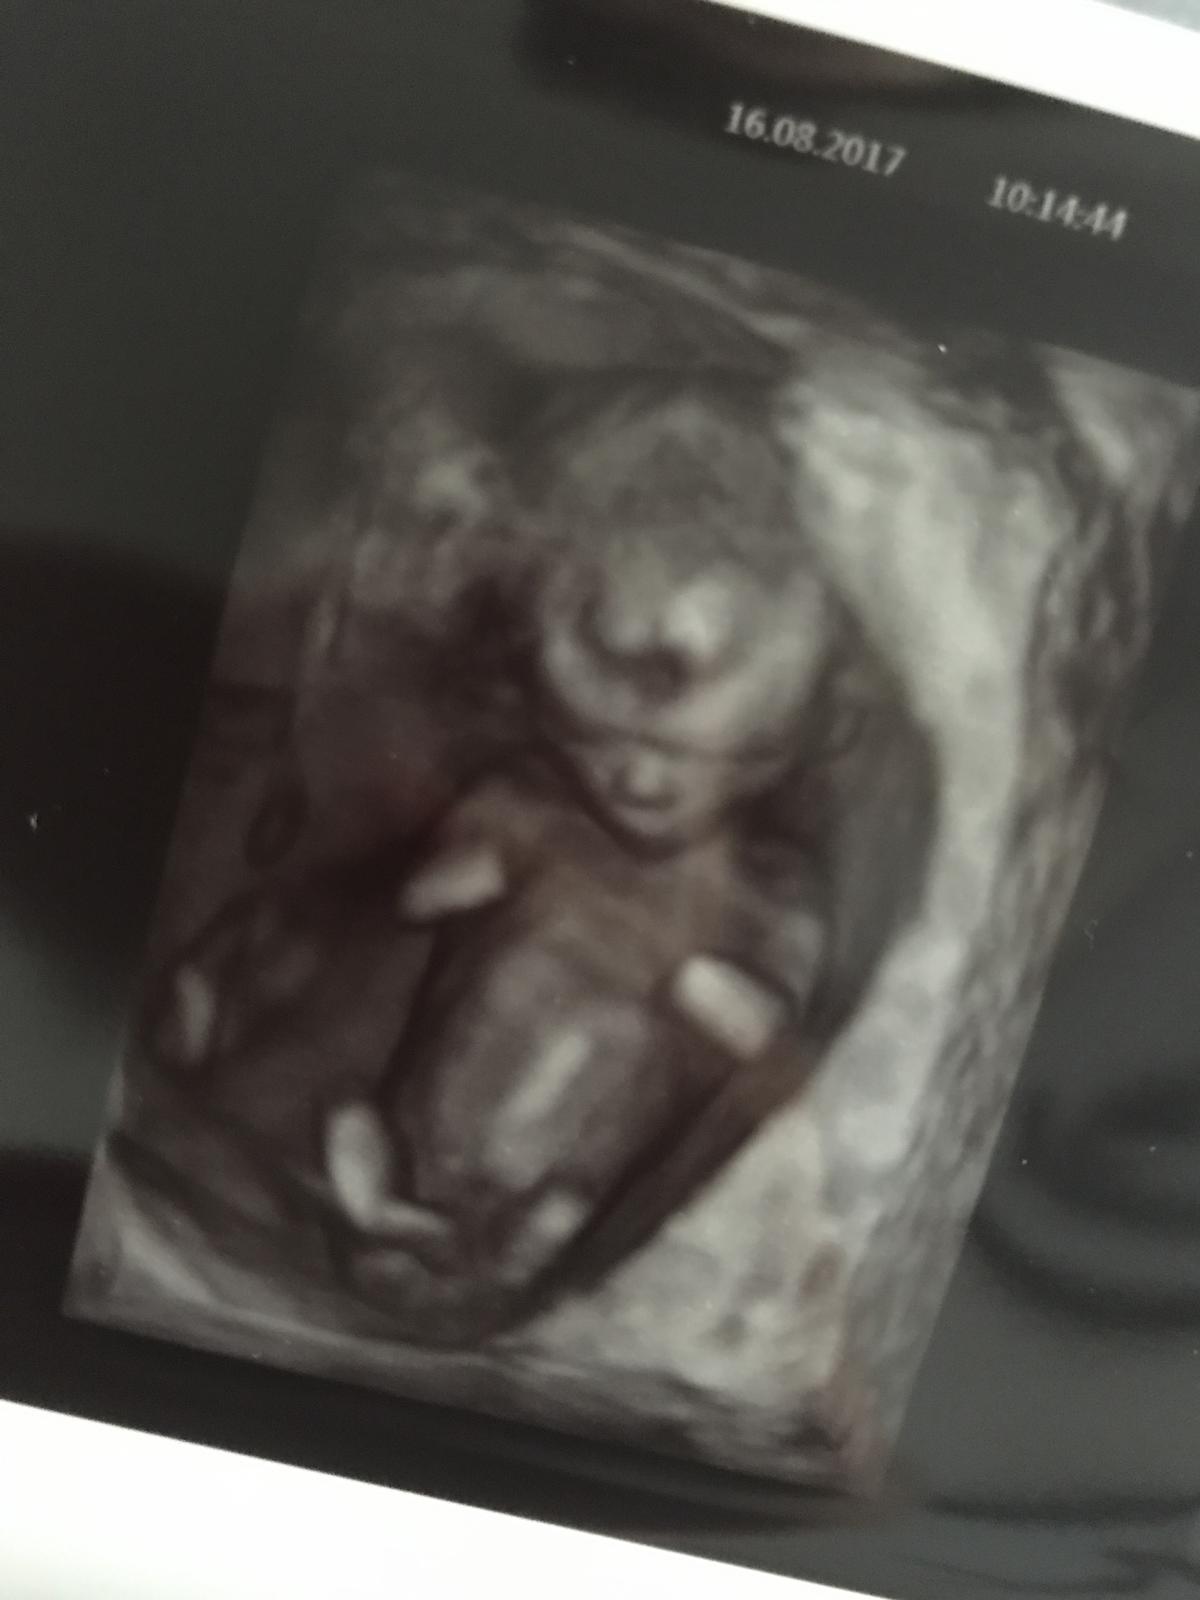

@mandlicka25 Zdravím, tak hlásím, že screening máme úspěšně za sebou. Měli jsme opravdu našeho p. dr. Štěpána ml. .Bylo to moc hezké. Viděli jsme jak klasický, tak 3D ultrazvuk, slyšeli tlukot srdíčka, dr. miminko změřil, zkontroloval nosní kůstku, šíjové projasnění a něco ohledně jater (už si přesně nepamatuji, co říkal), jen pohlaví nám zůstává stále utajeno (mimi bylo tak natočeno, že dr. nic neviděl). Ani nevím, jak to celé mohlo dlouho trvat, ale předchozí pár tam byl necelou čtvrt hodinku. Až mě to přišlo skoro líto, že jsme se tímto se Sanusem rozloučili, něco jsme se tam přece jen najezdili (hlavně díky OHSS). Tak přeju, ať vám to taky všechno dobře dopadne a budu čekat příští týden na zprávu od tebe 😉